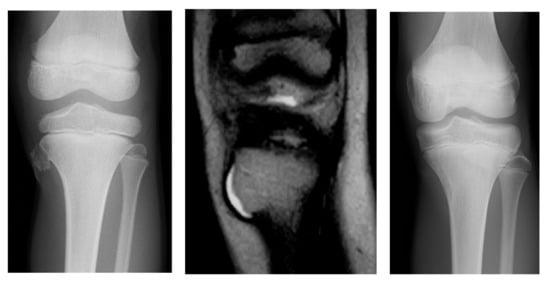

3.1.1. Case 1

3.1.2. Case 2